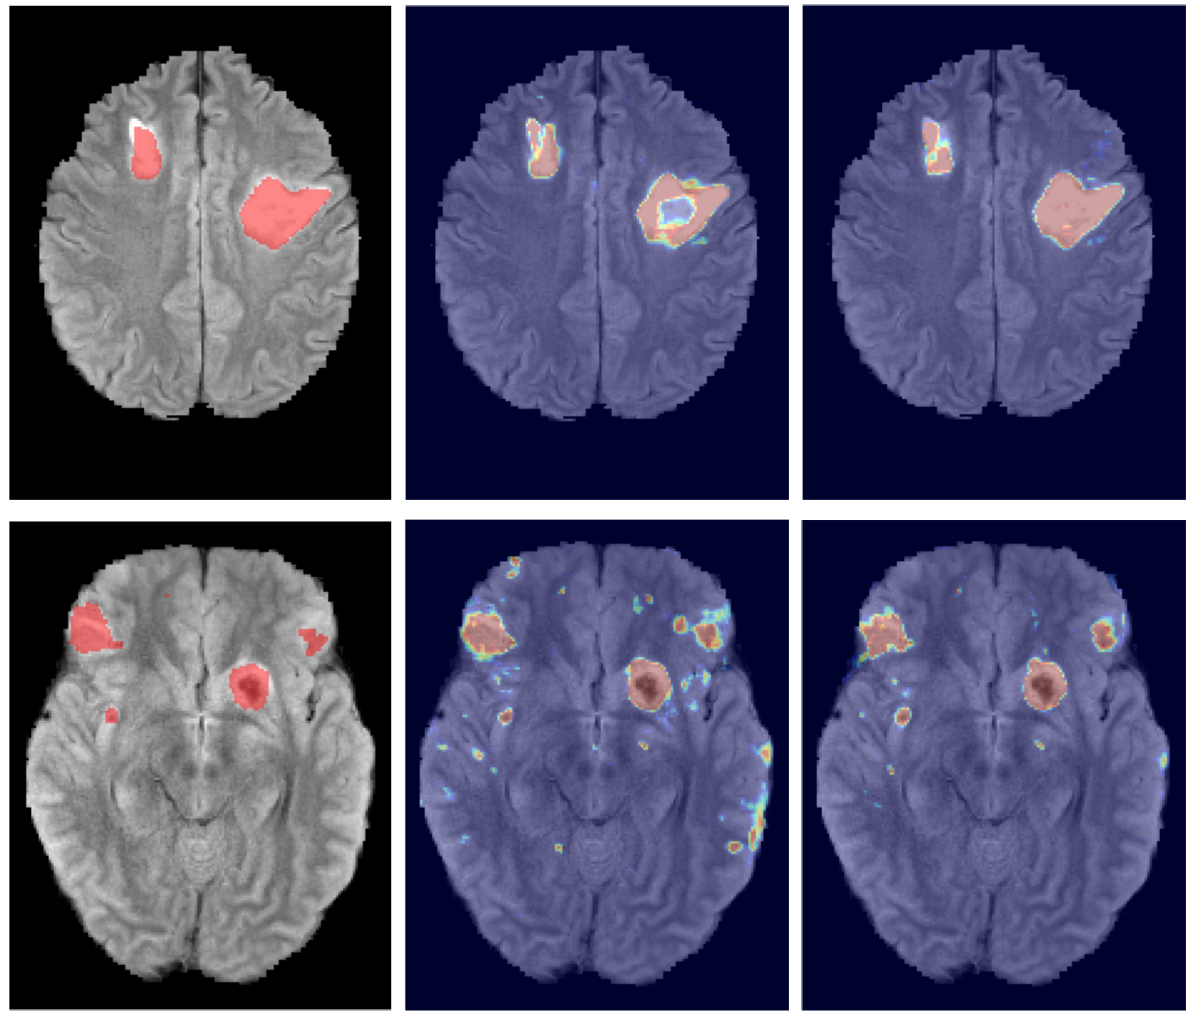

The final version of the proposed network architecture, referred to as “DeepMedic”, is built by extending the Deep+ model with a second convolutional pathway that is identical to the first one. Two hidden layers are added for combining the multi-scale features before the classification layer, resulting in a deep network of 11-layers (cf. Fig. 5). The input segments to the second pathway are extracted from the images down-sampled by a factor of three. Thus, the network is capable of capturing context in a 513superscript51351^{3} area of the original image through the 173superscript17317^{3} receptive field of the lower-resolution pathway, while only doubling the computational and memory requirements over the single pathway CNN. In comparison, the most recent 2D CNN systems proposed for lesion segmentation (Havaei et al. (2015); Pereira et al. (2015)) have a receptive field limited to 332superscript33233^{2} voxels.

Figure 9: (Rows) Two cases from the severe TBI dataset, showing representative improvements when using the multi-scale CNN approach. (Columns) From left to right: the MRI FLAIR sequence with the manually labeled lesions, predicted soft segmentation map obtained from a single-scale model (Deep+) and the prediction of the multi-scale DeepMedic model. The incorporation of greater context enables DeepMedic to identify when it processes an area within larger lesions (top). Spurious false positives are significantly reduced across the image on the bottom.

Figure 8 shows the improvement DeepMedic achieves over the single pathway model Deep+. In Fig. 9 we show two representative visual examples of this improvement when using the multi-scale CNN. Finally, we confirm that the performance increase can be accounted to the additional context and not the additional capacity of DeepMedic. To this end, we build a big single-scale model by doubling the FMs at each of the 9-layers of Deep+ and adding two hidden layers. This 11-layers deep and wide model, referred to as “BigDeep+”, has the same number of parameters as DeepMedic. The performance of the model is not improved, while showing signs of over-fitting.